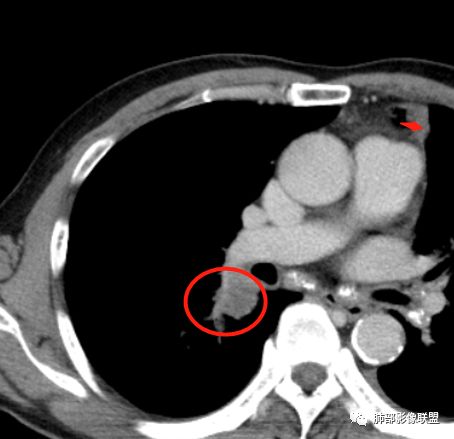

Coke with ice:

吴老师标记的这个支气管结节有点意思。其他的真是想不到鳞癌

雪上一枝蒿(陈显静):

这个是9月7号的平扫CT

右下肺病理没有报癌

但是化疗2次后也缩小了

背段入口在CT上也可以见到了

回头看尖段的分支和背段肯定是堵了,两处应该都是鳞癌,右肺基底段的就不知道了。

前段堵了

右下背还是考虑恶性可能

支气管镜下明显见到新生物了,病理取到表面粘膜。

鳞癌起源于支气管粘膜,是气道中最常见的恶性肿瘤,易造成支管壁增厚,并突入腔内形成结节,造成狭窄、阻塞或截断;早期鳞癌表现为沿支气管生长的梭形结节或局限性增厚,辖区内常出现阻塞性炎症,这样的病灶赢多平面重建并仔细观察支气管改变;如果有支气管壁偏心性增厚伴管腔狭窄或腔内结节形成,都要想到早期鳞癌的可能性,复查或内窥镜检查是必要的。

鳞癌好发于中老年人,与吸烟关系密切,如果发现不易吸收的,或同一部位反复无常局限性肺炎,我们应当仔细观察支气管壁的病变除外阻塞的可能;该病例右肺下叶背段及左肺上叶支气管有肿块及管壁的增厚,应当想到恶性可能。

1.右肺下叶支气管壁增厚,后壁为主,且显示壁外结节,未见异常强化。这样的结节和蔓延方式一般会高度怀疑气道来源的恶性肿瘤,如鳞癌、粘液表皮样癌、腺样囊性癌等。可惜没有相应病理学资料支持。

右肺下叶近膈面球形病灶缺乏恶性病灶特点,没有分叶、毛刺、牵拉等,应当符合炎性。